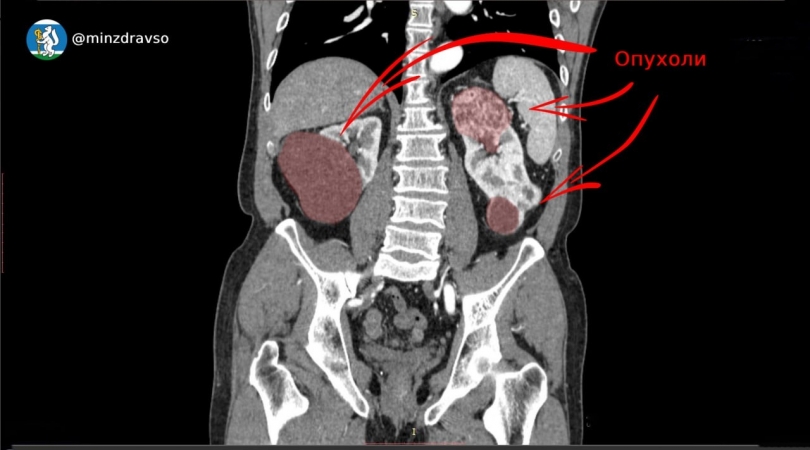

Патологию у мужчины обнаружили во время планового медосмотра. При углубленном обследовании выяснилось, что правая почка более чем наполовину поражена опухолью диаметром свыше 6 см. Орган пришлось удалить.

Но и левая почка оказалась поражена двумя крупными новообразованиями. Чтобы сохранить ее функцию, онкоурологи провели сложнейшую операцию по удалению опухолей общим размером 12 см, сохранив 70% здоровой ткани.